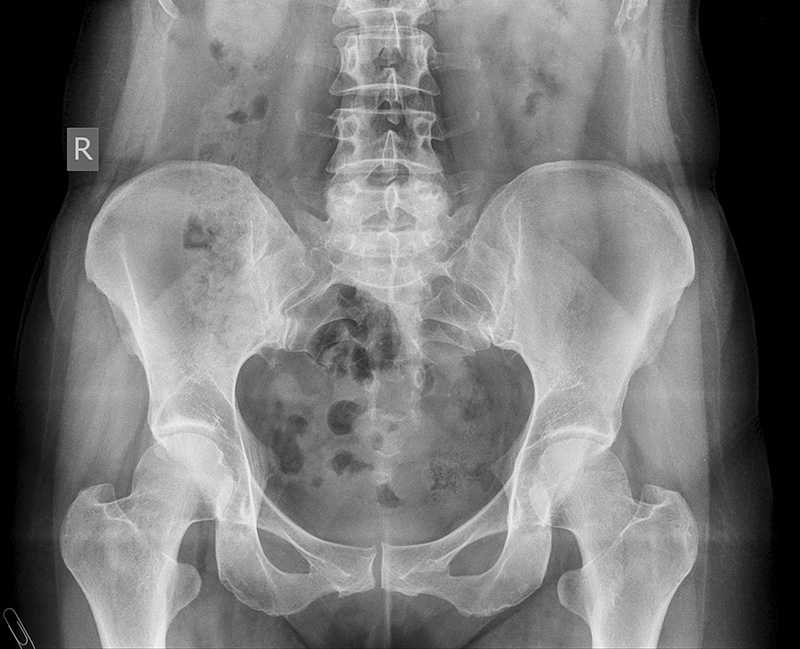

3. Правосторонний сколиоз поясничного отдела позвоночника, сакрализация тела L-5 позвонка

7. Рентгенография костей таза- без патологии

14. Рентгенография тазобедренных суставов -В межвертельной области бедренной кости определяется перестройка костной структуры, с четкими склеротическими контурами, медиальный контур коркового слоя истончен, но сохранен. Киста имеет овальную форму, размерами 40 на 25 мм.